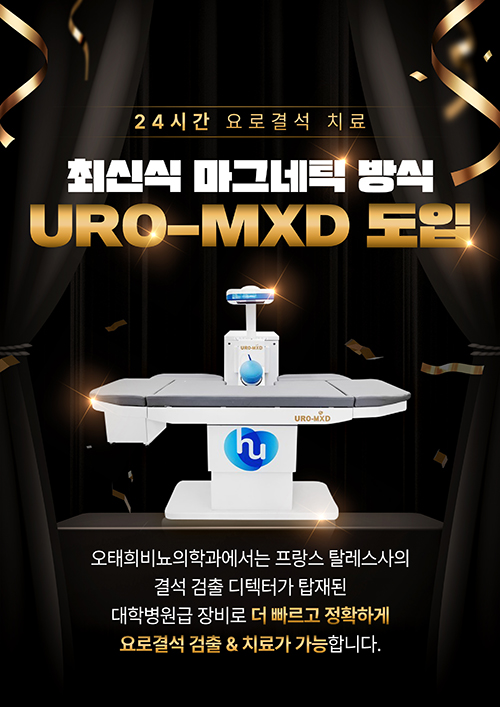

장비 소개

체외충격파 쇄석기

체외충격파 쇄석기 -

- URO-MXD 도입